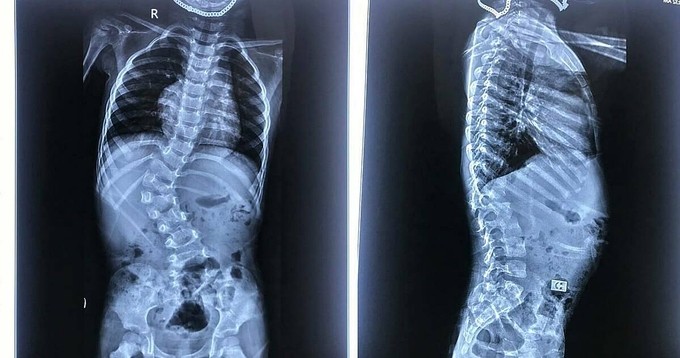

Cột sống bé trai 3 tuổi, ở Thanh Hóa, cong vẹo 66 độ, bác sĩ phải can thiệp ngay bởi trì hoãn vài năm nữa sẽ không thể phẫu thuật nắn chỉnh.

Bé được phát hiện bất thường cột sống khi 2 tuổi, bác sĩ chẩn đoán vẹo cột sống ngực - thắt lưng bẩm sinh mức độ lớn do dị tật nửa đốt sống L1. Khi ấy bé vẫn đi lại được nhưng cột sống lệch, cúi ngửa khó khăn, hạn chế vận động do đau lưng.

Bác sĩ Nguyễn Duy Thụy, khoa Chấn thương - Chỉnh hình Cột sống, Bệnh viện Trung ương Quân đội 108, cho biết hiện tình trạng biến dạng cột sống của bé đã ở mức độ nặng, góc vẹo 66 độ. Nếu đợi khi cháu được 6 tuổi trở lên thì không thể phẫu thuật nắn chỉnh.

Phim chụp Xuang bệnh nhi trước khi mổ. Ảnh: Bệnh viện cung cấp.